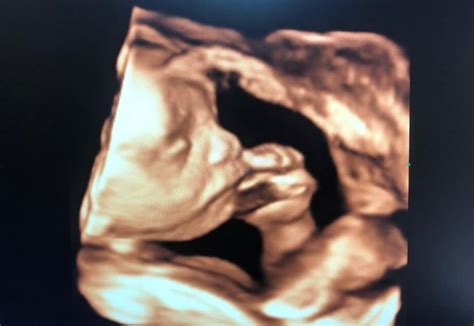

După 11 săptămâni de gestație, fătul este suficient de dezvoltat din punct de vedere anatomic și al dezvoltării organelor interne pentru a permite realizarea unei analize detaliate. Această etapă oferă posibilitatea depistării precoce a unor modificări specifice asociate cu anomalii cromozomiale și alte afecțiuni. Anumite organe, precum inima, sunt complet formate structural și funcțional, urmând ca în lunile următoare de sarcină doar să crească în dimensiuni și să capete o textură mai rezistentă. În contrast, plămânii și sistemul nervos central (creierul) vor continua să sufere numeroase transformări, atât la nivel de structură, cât și de funcție.

În această perioadă, fătul capătă aspectul unei ființe umane, deși poate prezenta o ușoară disproporție prin dimensiunea mai mare a craniului comparativ cu adultul. Se pot observa o gamă variată de mișcări ale corpului și membrelor.